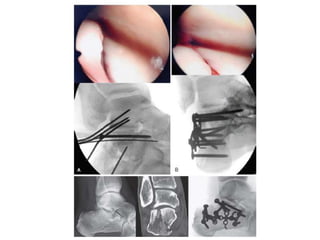

Tratamiento quirúrgico

• Afectación carilla posterior

• 25% de la Art calcáneo

cuboidea

• Fracturas Abiertas

• Fracturas desplazadas de la

tuberosidad.

• Signo del pliegue

• Cirugía antes de las 3

semanas

RIF - Fijación de placa y tornillo.

Indicaciones

• Mala posición y forma del

talón.

Afectación articular

desplazada.

No existen

contraindicaciones

médicas para el cuidado

quirúrgico.

Fracturas abiertas

Pacientes conformes

<60 años

Pacientes sin

comorbilidades médicas

o comorbilidades

individuales controladas

No fumadores

Ventajas

• Reconstrucción de la

superficie articular.

Reconstrucción de

altura, anchura y longitud

del pie.

No varus

No hay necesidad de

calzado especializado.

AO Surgery Fundation Joseph Schatzker, Richard Buckley, Andrew Sands

RIF - Fijaciónde placa y tornillo. Indicaciones • Mala posición y forma del talón. Afectación articular desplazada. No existen contraindicaciones médicas para el cuidado quirúrgico. Fracturas abiertas Pacientes conformes <60 años Pacientes sin comorbilidades médicas o comorbilidades individuales controladas No fumadores Contraindicaciones • Incumplimiento Afecciones médicas no controladas (diabetes) Vasculopatía Fumadores impenitentes Edad mayor de 60 Extremadamente sedentario Ventajas • Reconstrucción de la superficie articular. Reconstrucción de altura, anchura y longitud del pie. No varus No hay necesidad de calzado especializado. AO Surgery Fundation Joseph Schatzker, Richard Buckley, Andrew Sands